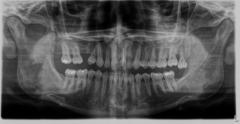

Want to get rid of my horrendous bruxism.